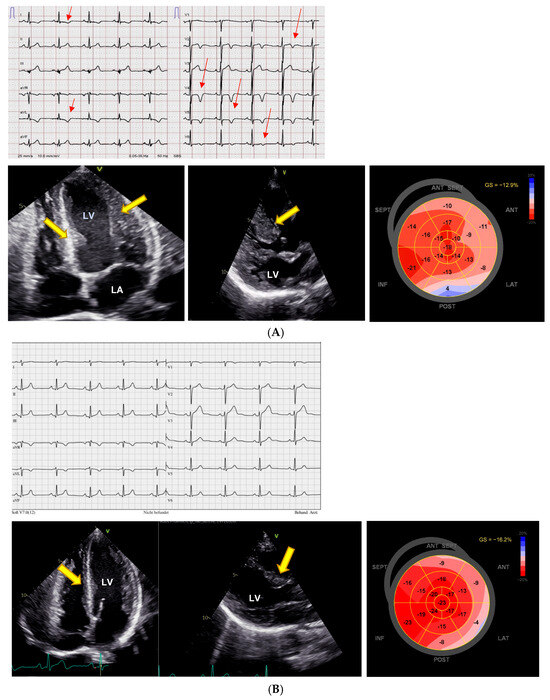

An 82-year-old man had been taking VEN for more than 8 years in a dose of up to 187.5 mg/day. LVEF had been documented as normal in the past. In spring 2023, he presented with severe heart failure, pleural effusions, edema, renal failure, massive increase in NT-proBNP (22,743 ng/L, age-adjusted normal < 450 ng/L), a dilated LV with severely diminished LVEF of 20% and impaired LV GLS (Figure 3A). Coronary angiography ruled out significant coronary artery disease. Other medications included bisoprolol, sacubitril/valsartan, torasemide, empagliflozin, tamsulosin, insulin, immunoglobulin treatment (i.v., every 2 weeks), and warfarin. The patient was also diabetic and had a history of necrotizing myositis, possibly due to statin treatment (thus the immune treatment), along with a history of sensory polyneuropathy, diabetes, and chronic issues related to previous subarachnoid hemorrhage. VEN was subsequently reduced to 75 mg/day. At the last follow-up in November 2024, he was asymptomatic; the biplane LVEF was 56% (normal 52–72%), and LV strain was borderline with a GLS of −16.7% (Figure 3B). NT-proBNP was normal at 227 ng/L. VEN serum concentrations were within normal limits (VEN 0.36 µmol/L, O-Desmethyl-VEN 0.18 µmol/L, VEN + O-Desmethyl-VEN 0.53 µmol/L; normal range 0.36–1.44 µmol/L). There was also stage 3b renal impairment, with an estimated glomerular filtration rate (eGFR) of 37 mL/min/m2.

Figure 3.

Severe impairment of LV ejection fraction parallel to reduction in LV strain, reversible after dose reduction. (A) During high-dose venlafaxine 187.5 mg therapy there is left ventricular (LV) hypertrophy (yellow arrows), a significantly reduced left ventricular ejection fraction (LVEF) of 20%, and severely impaired left ventricular global longitudinal strain (GLS) of −5.7%, indicating marked systolic dysfunction. LV = left ventricle, LA = left atrium. (B) Under venlafaxine 75 mg, a regression of left ventricular (LV) hypertrophy (yellow arrow) was observed, with an improvement in LV ejection fraction (LVEF) to 49% and an increase in left ventricular global longitudinal strain (GLS) to −16.7%.